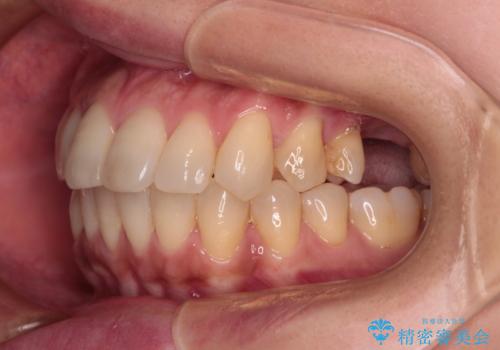

- 全体的なデコボコと、以前抜歯した歯のスペースを閉じた部分が気になるとのことで来院された患者様です。

左上第一大臼歯を抜歯した際に、スペースを閉じたそうですが、歯が傾斜してものが挟まって不快とのことでした。

インビザライン矯正で全体の歯列と整えるとともに、左上第一大臼歯部にはスペースを作り、インプラントによる補綴治療を行うこととしました。